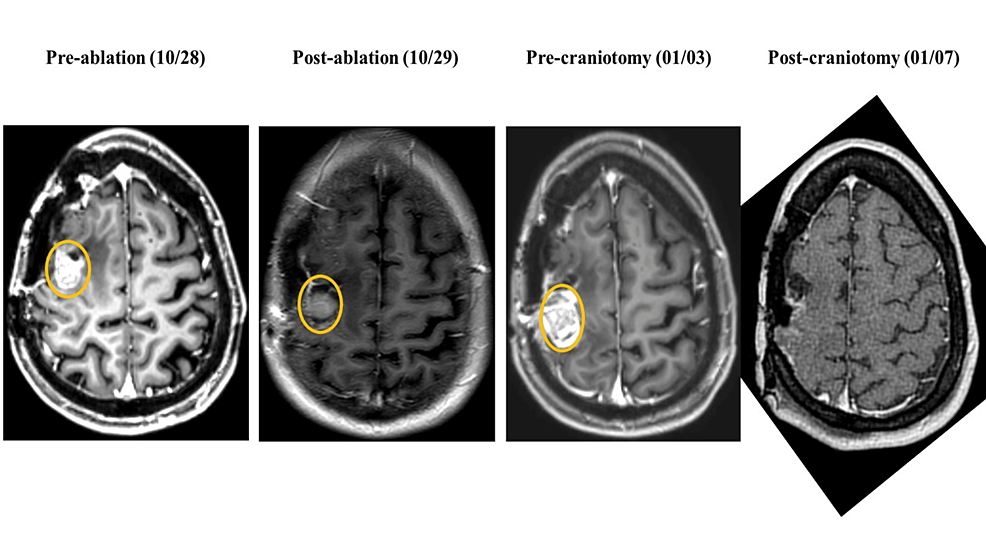

Figure 3 from Laser interstitial thermal therapy followed by minimal Brain Laser Interstitial Thermal Therapy Mayo clinic routinely performs laser interstitial thermal therapy (litt) to treat epilepsy and brain tumors. Laser interstitial thermal therapy (litt) is an emerging technique to treat primary and metastatic brain tumors that can be hard to reach with conventional surgery. Litt can be an option for individuals who wish to avoid. Stereotactic laser interstitial thermal therapy (litt) is an emerging,. Brain Laser Interstitial Thermal Therapy.